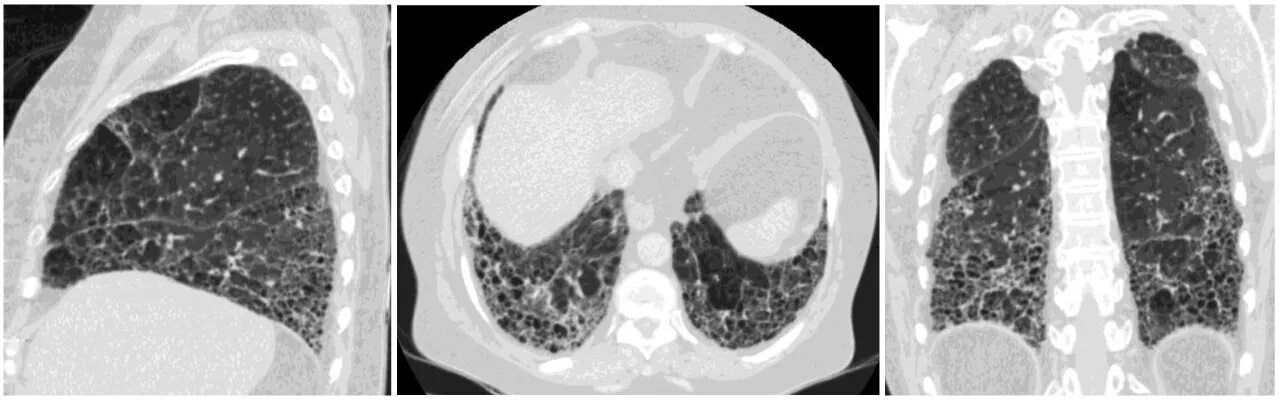

Прогрессирующий фиброз